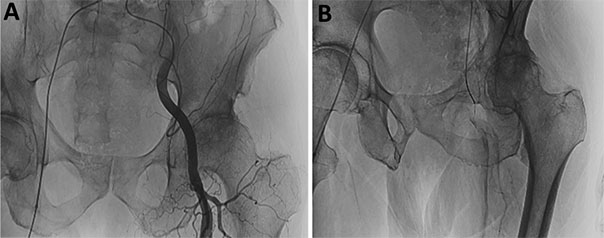

Hüftgelenk